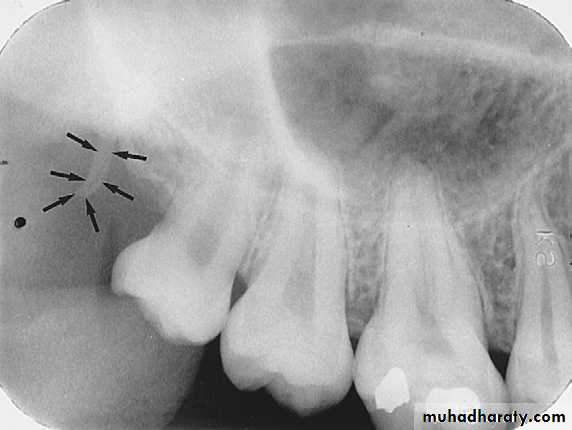

Pterygoid Plates

Pterygoid plates lie immediately posterior to the tuberosity of the maxilla. The image of these two plates is extremely variable, and they do not appear at all on many intraoral radiographs of the third molar area. When they are apparent, they almost appear as single radiopaque homogeneous shadow without any evidence of trabeculationHAMULUS:

The hamulus also known as the hamular process is a small hook like projection of bone extending from medial pterygoid plate of sphenoid bone it locater posterior to maxillary tuberosity region. Radiographically, the hamulus appears as a radiopaque hook like projection posterior to maxillary tuberosity area.